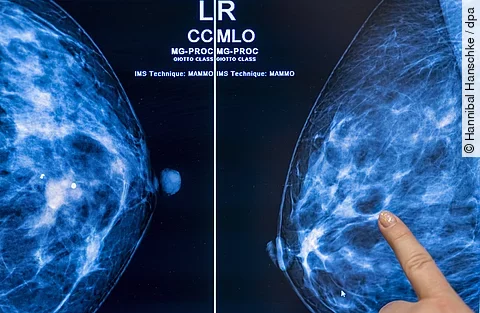

Im Zuge des Programms können Frauen alle zwei Jahre eine Röntgen-Untersuchung der Brust zur Früherkennung in Anspruch nehmen. Solche bildgebenden Verfahren können schon sehr kleine Tumoren sichtbar machen, die sich noch nicht ertasten lassen. Frauen, bei denen Symptome bestehen oder ein ärztlicher Verdacht auf Brustkrebs vorliegt, erhalten Mammografien zudem im Rahmen der allgemeinen Versorgung.